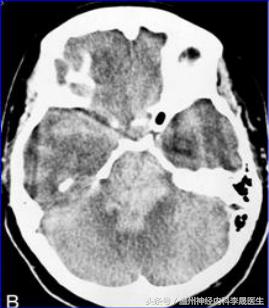

壳核出血

壳核出血(大)

壳核出血(A)小壳核范围内的出血,(B)侵犯了内囊,(C)血肿压迫侧脑室